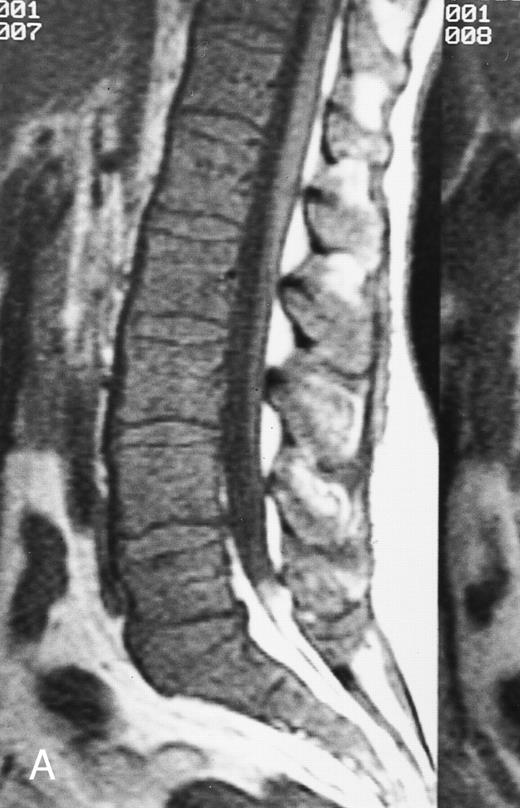

Normal appearance of spinal bone marrow in a 45-year-old woman: T1-weighted (500/11, TR/TE) (A) and T2-weighted, fat-suppressed fast spin echo (4000/96, TR/TE, ET 16) (B) sagittal MR images of the lumbar spine. Note increased signal of the vertebral bodies, relative to the intervertebral discs in (A) and increased deposition of fatty marrow around the basivertebral veins (arrowheads). On the T2-weighted image, normal intervertebral discs are brighter than the vertebral bodies; low signal in the L4-L5 and L5-S1 discs is due to degenerative changes (arrows).